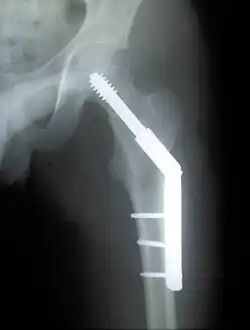

Laterale Schenkelhalsfraktur

Frakturen in der Basis des Schenkelhalses werden, in Abhängigkeit vom Dislokationsgrad, oft gelenkerhaltend, mit einer Osteosynthese versorgt. Das Behandlungskonzept entspricht weitgehend dem der pertrochantären Femurfrakturen. Verschiedene Verfahren können verwandt werden, unter anderem die Gammanagel-Osteosynthese, die Versorgung mit Dynamischer Hüftschraube (DHS) und ähnliche.[13]